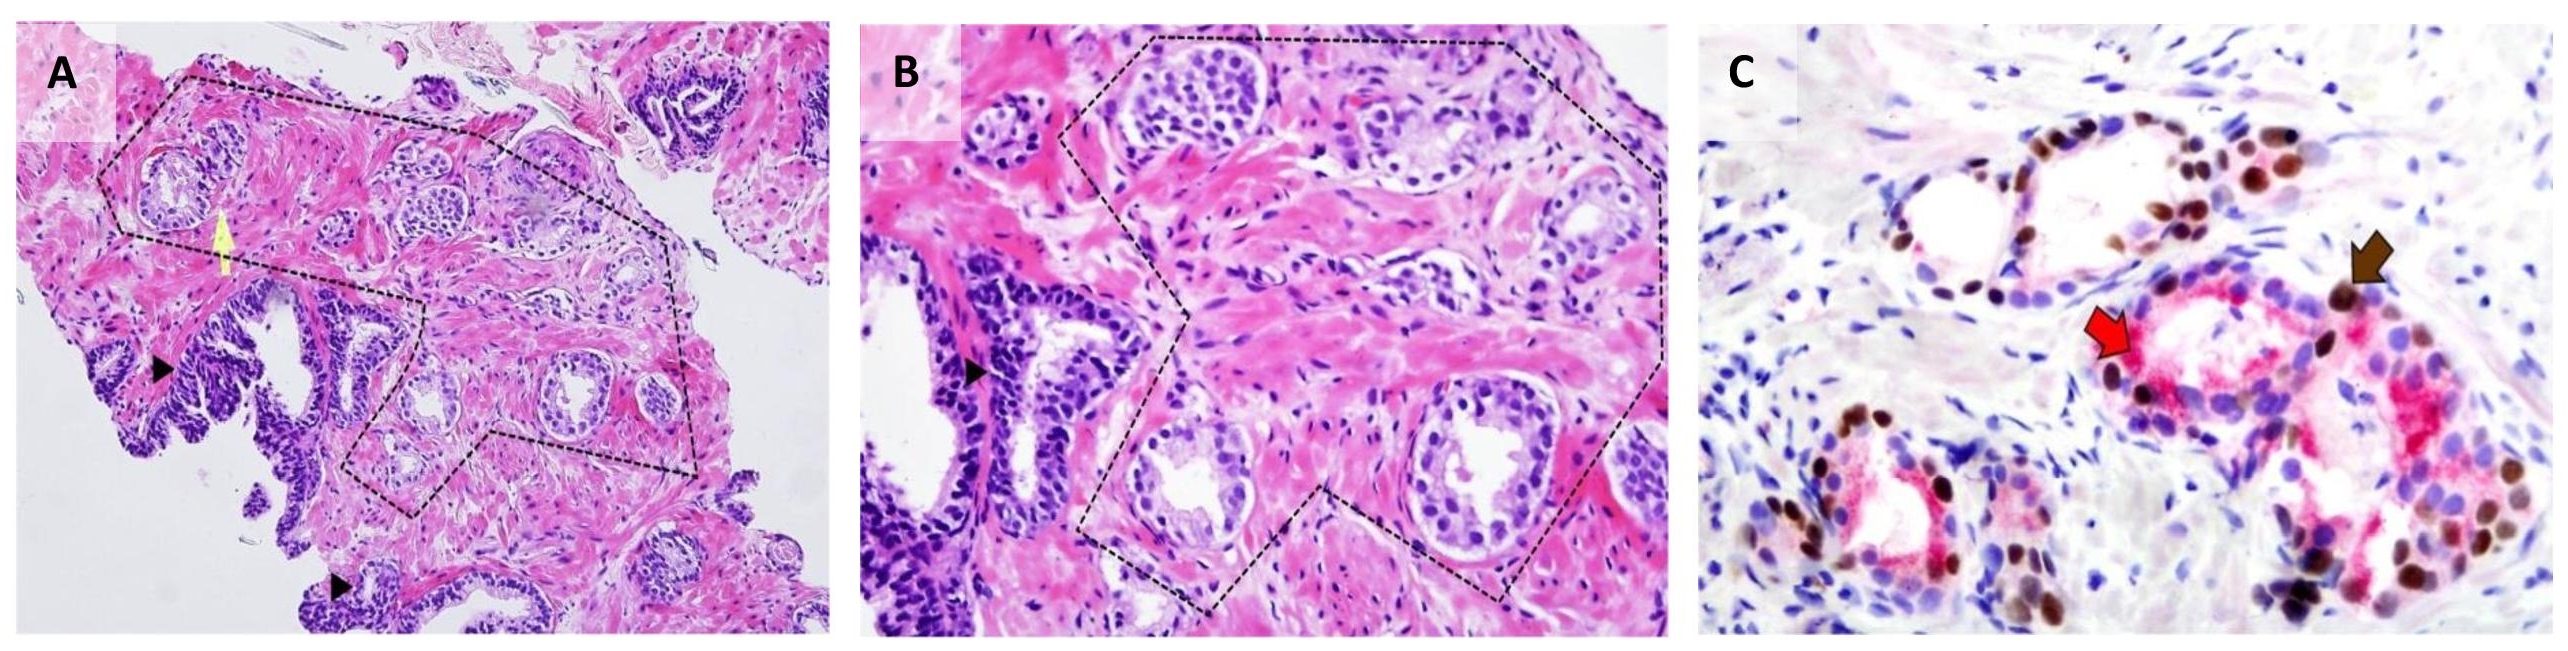

We report a case of a 62-year old male who presented with urinary tract infection. Work-up revealed an enlarged prostate gland weighing 25 grams by ultrasonography; and an elevated prostate-specific antigen (PSA) of 13 ng/mL. He underwent a transrectal ultrasound-guided (TRUS) prostate biopsy reported as benign prostatic hyperplasia with high-grade prostatic intraepithelial neoplasia in another institution; hence, he was advised PSA monitoring. A month after the procedure, his PSA decreased to 3.7 ng/mL. However, the patient was lost to follow-up. On consult few months later, PSA was noted to have increased to 6.08 ng/mL. He underwent another TRUS biopsy (now assessed by the primary author), which revealed a small focus of atypical glandspresent suspicious for prostatic adenocarcinoma, in one core. These few well-formed, individual, atypical glands were seen seemingly infiltrating in between benign acini. The glands of interest show rigid lumina and multilayered neoplastic cells which have enlarged hyperchromatic nuclei with rare prominent nucleoli and amphophilic cytoplasm. Immunohistochemical analysis for p63 (antibody clone 7JUL, Biocare Medical®), high molecular weight cytokeratin (HMWCK, antibody clone 34βE12, Leica Bond®), and α-methyl acyl coenzyme-A racemase (AMACR, antibody clone 13H4, Dako®) in a PIN4 cocktail was performed in accordance with the recommendation by International Society of Urological Pathology (ISUP).[8] The atypical glands showed granular luminal and cytoplasmic positivity for AMACR; and no HMWCK-expressing basal cells were identified among these glands. Surprisingly, some of their nuclei were strongly positive for p63 (Figure 1). The final diagnosis was prostatic adenocarcinoma, involving 5% of one core, with diffuse aberrant staining for p63. A Gleason score of 3+3=6 would be designated if this was a classical acinar prostatic adenocarcinoma.

Figure 1. Prostate core biopsy from the study case. (A)Atypical glands (within dashed lines) with rigid luminal borders are seen infiltrating between benign acini (arrowhead) (H&E 100x). (B) On higher magnification, the cells have enlarged hyperchromatic nuclei with prominent nucleoli and moderate amount of amphophilic cytoplasm (H&E 400x). (C) Immunohistochemical staining for PIN4 decorates secretory luminal cells with nuclear and cytoplasmic immunoreactivity for p63 (brown arrow) and AMACR (red arrow), respectively, and lack of basal staining for HMWCK (PIN4 400x).